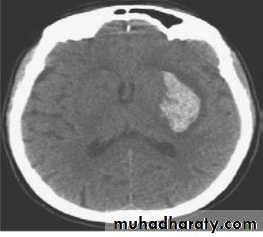

The test of choice for making the diagnosis is a non– contrast-enhanced CT scan that shows areas of hemorrhage as zones of increased density, which may or may not have associated regions of decreased density indicating infarction.